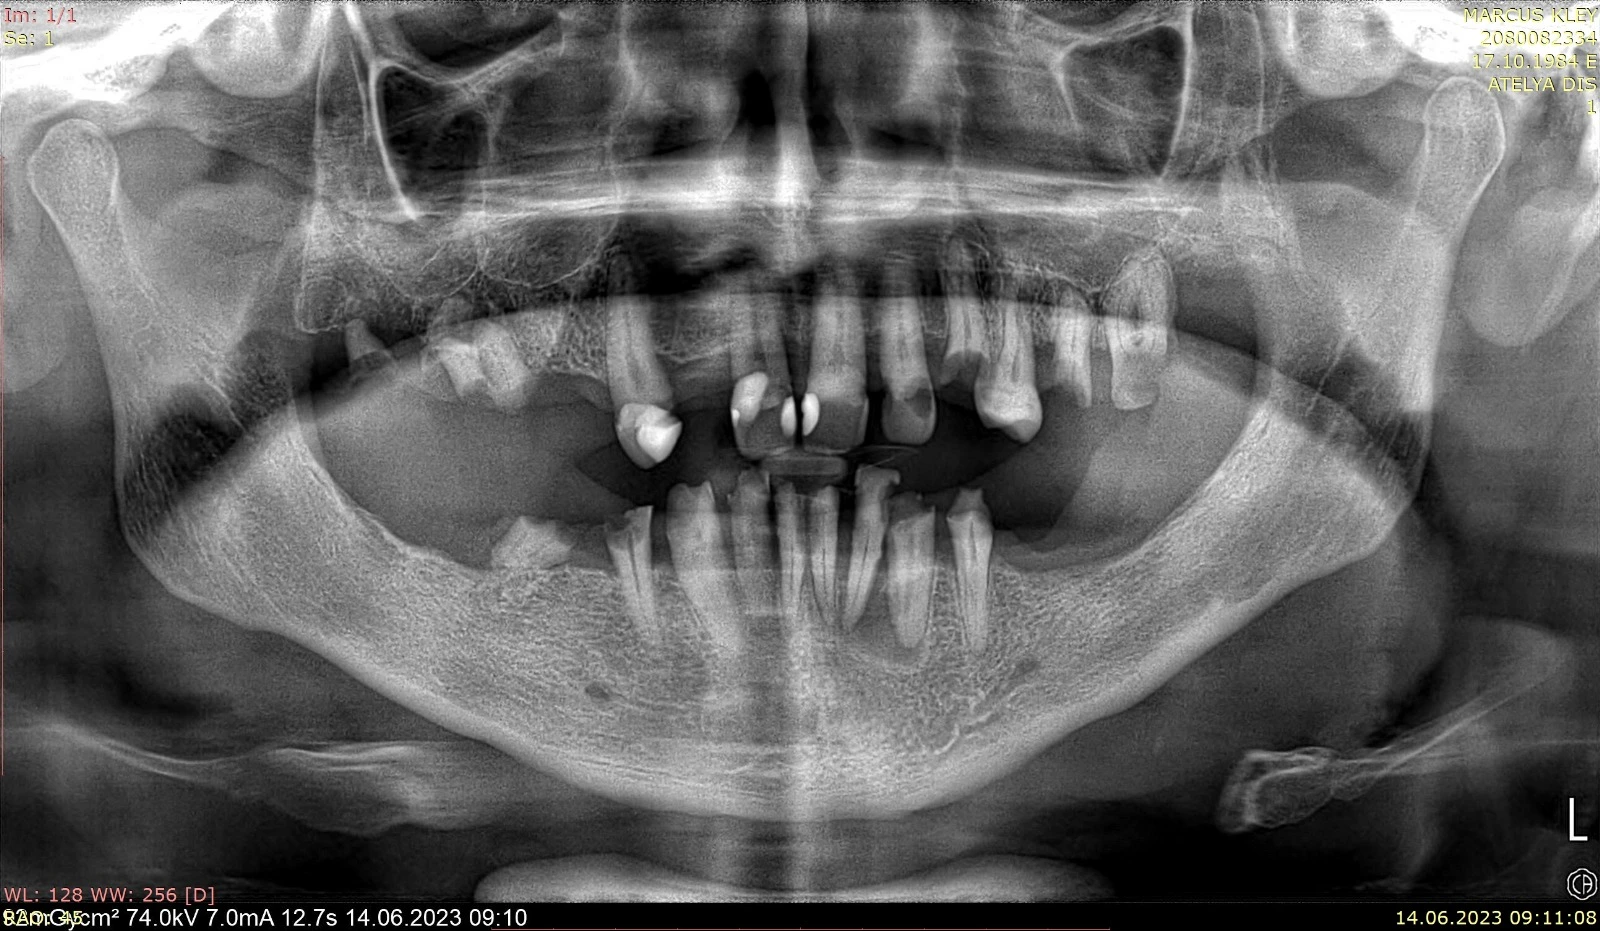

Tooth loss affects more than just your ability to chew; it can impact your speech, self-confidence, and overall facial appearance. All-on-6 dental implants offer a modern, full-arch restoration for patients with multiple missing teeth, providing a stable, comfortable, and permanent solution. In this technique, six biocompatible titanium implants are strategically placed in the jawbone to support full-arch prosthetic teeth. These implants act as a powerful anchor, creating a secure foundation for your new smile.

While All-on-6 dental implant treatment often yields fast and effective results in patients with sufficient bone volume, we achieve high success rates even in cases with insufficient bone density through our solution-oriented approaches. Utilizing bone grafting (bone powder) and advanced surgical techniques, we adapt our treatment planning to the patient's anatomical limits, bringing the comfort of All-on-6 to even the most challenging cases.

Regardless of bone quantity, this approach ensures every patient is treated with a long-lasting roadmap best suited to their biological structure. This optimization stage creates an unshakable foundation for the titanium frame and aesthetic restorations built upon it. Furthermore, thanks to Zygomatic, Pterygoid, and Nasal implants, we possess the clinical equipment and expertise to perform complex treatments for challenging cases in a very short timeframe.